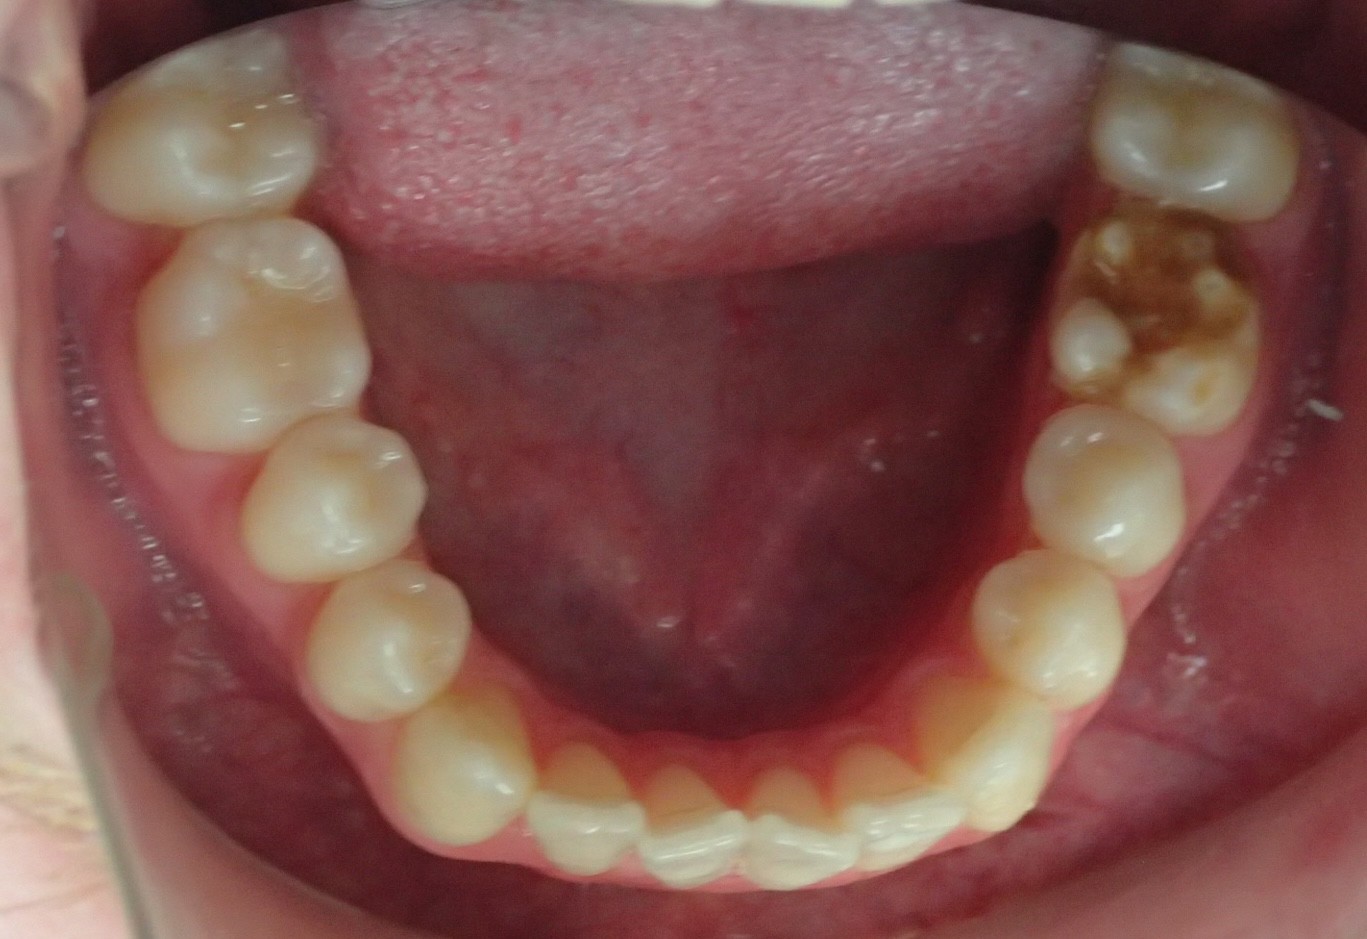

Diagnosis: Class III malocclusion, edge-to-edge anterior relationship, lower anterior crowding

Initial treatment

INTRAORAL